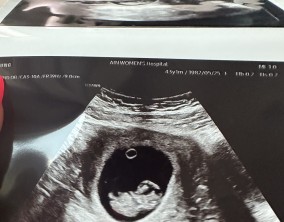

기대보다 먼저 찾아온 선물 같은 순간

이경훈 원장님께서 친절하고 꼼꼼하게 신경 써 주셨고, 간호사 분들께서도 하나하나 자세히 설명해 주시며 공감해 주셔서 치료 과정이 훨씬 편안하게 느껴졌습니다. 의료진 모두…